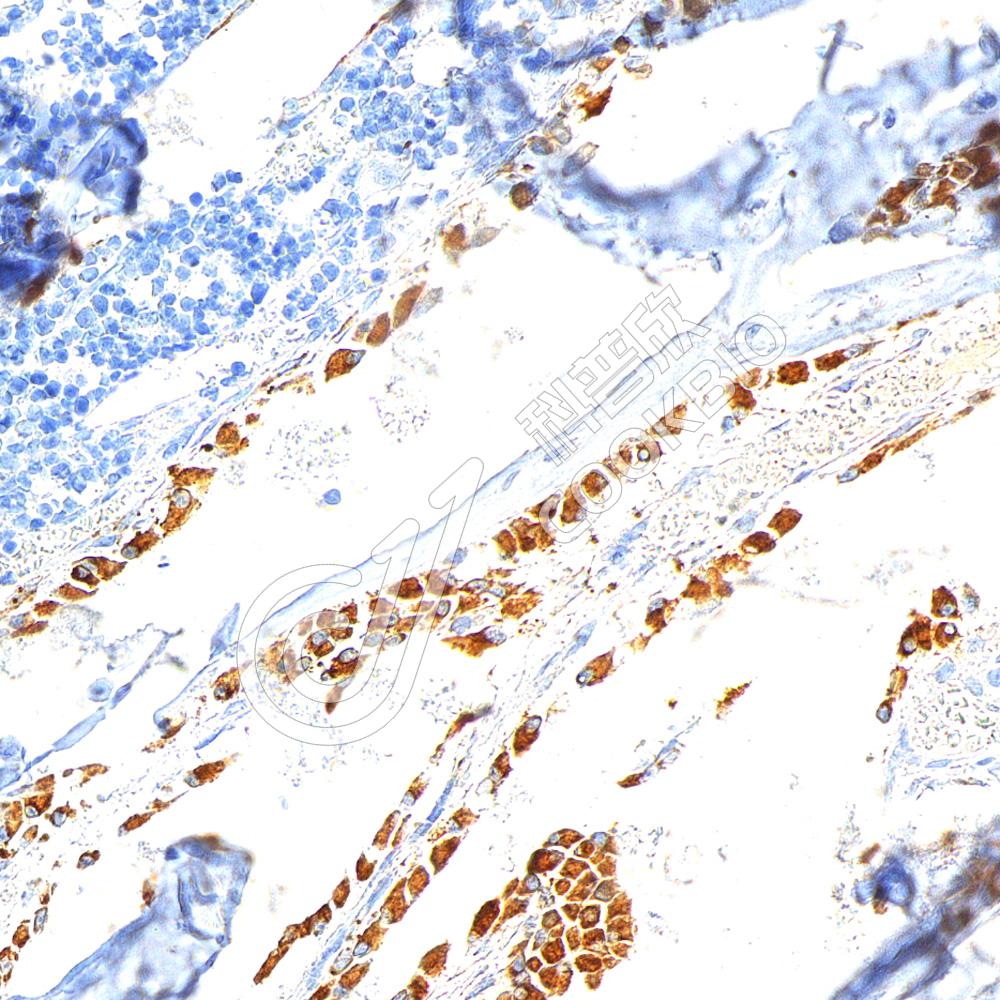

IHC检测Osteocalcin蛋白(货号 K2377052).

样品: 大鼠骨, 4%多聚甲醛 (货号KSG1101) 固定12-24小时.

抗原修复: 柠檬酸抗原修复液(干粉, pH 6.0) (KSG1201), 高压锅均匀喷气计时2分钟.

—抗: 1: 600稀释, 4℃ 孵育过夜.

二抗: S-vision免疫组化多聚二抗(山羊抗小鼠), 即用型(货号KB3903), 室温孵育20分钟.